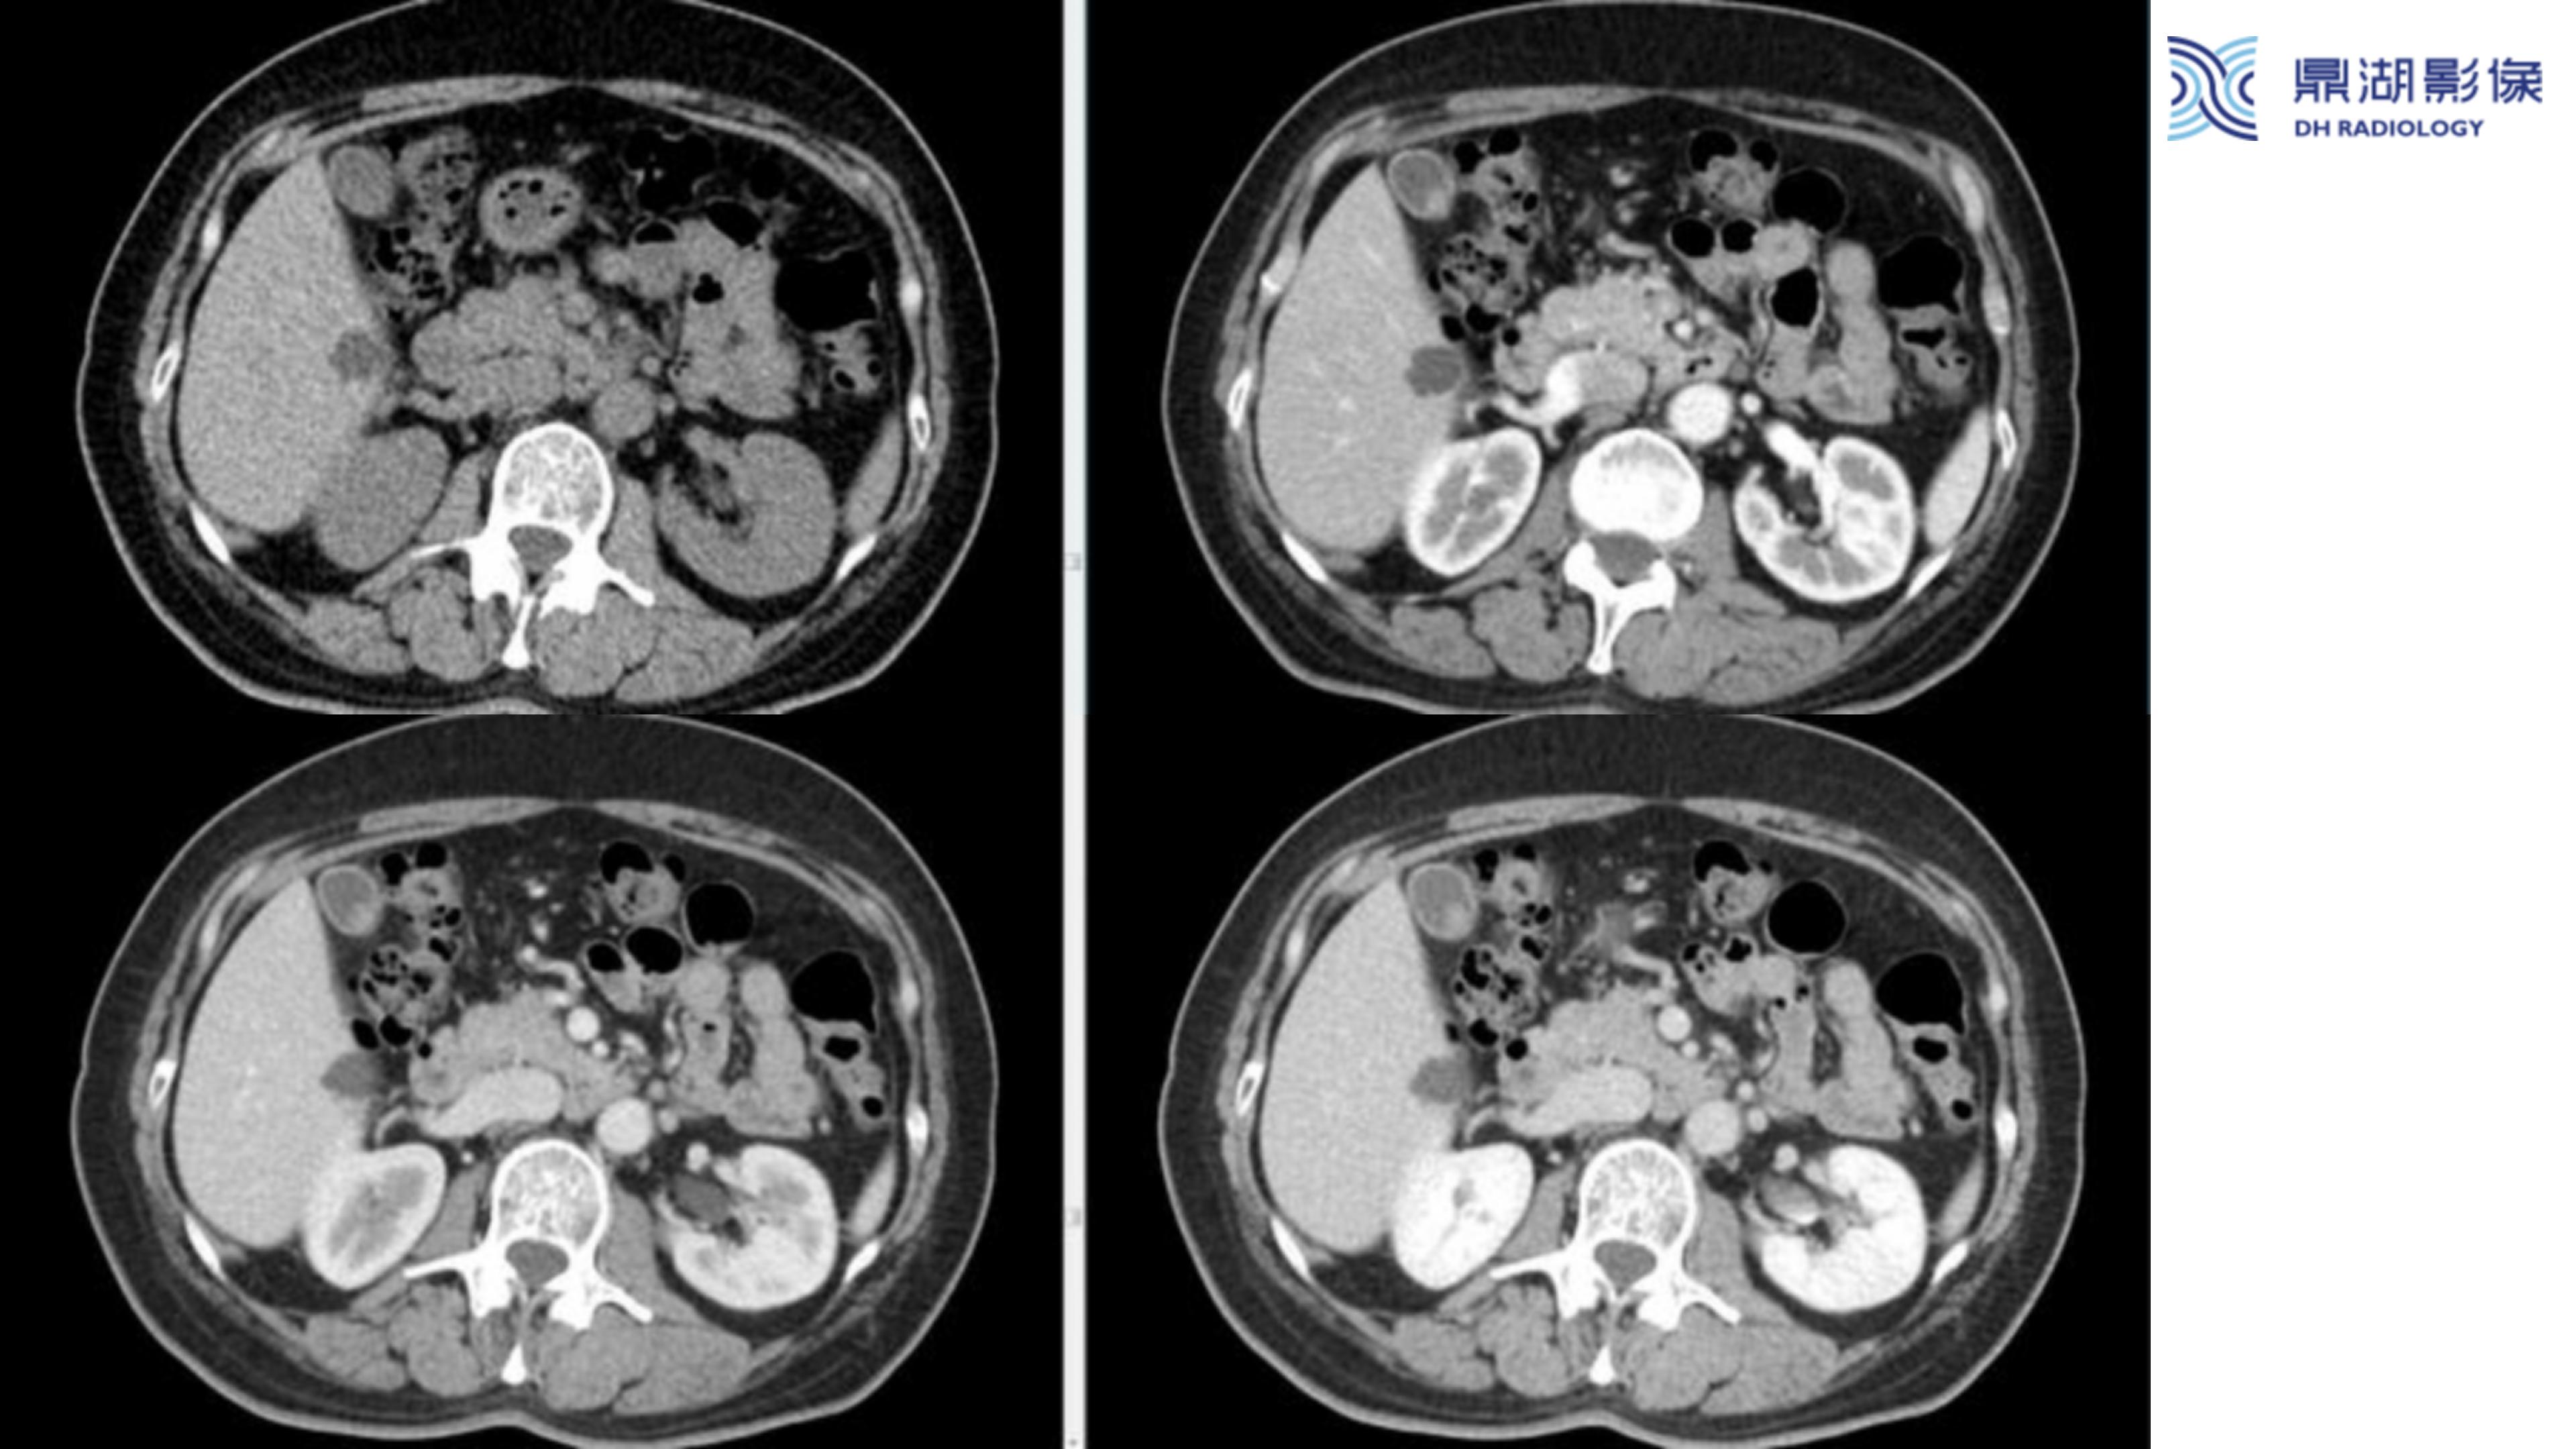

胆囊癌-鼎湖社群读片病例